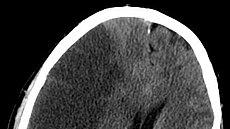

经过积极治疗 , 刘先生的状况却始终不见好转 。 他逐渐出现了意识障碍 , 头颅CT显示大面积脑梗塞 。 由于脑梗塞面积过大 , 他陷入了昏迷状态 , 最终影响到呼吸中枢 , 并逐渐出现了呼吸衰竭 , 最后不幸离世了 。